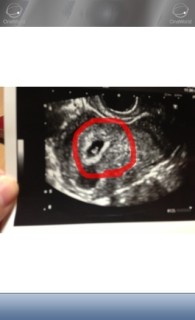

前回流産しているので一週間ぶりに受診。 先週も心臓ピコピコで今回もピコピコ♩ へその緒や脳まで確認できました!